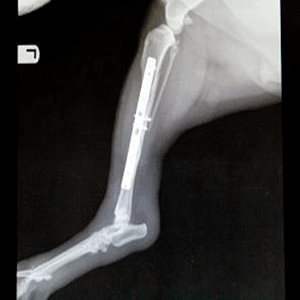

When your pet is faced with a medical condition that has nonspecific or common symptoms with unknown underlying causes, having diagnostic tools can make a big difference between the best diagnosis and a mediocre one. Here at Parkland Veterinary Hospital, we have advanced diagnostics capabilities at our disposal. Our capabilities include state of the art medical equipment and technology such as onsite Digital Radiographs, Ultrasound and Endoscopy by an expert visiting specialist, digital dental X-ray unit, digital monitoring of vital signs, point of care displays in each exam room to help with client communication, dental drill with a scaling and polishing unit, Video Otoscope, microscope, and much more.

- X-ray/Radiographs

- your pet has broken limb or suspected broken limb (limping or favoring leg)